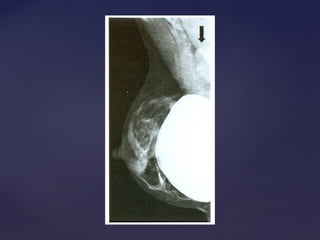

 Mamoplastia redutora ou implantes